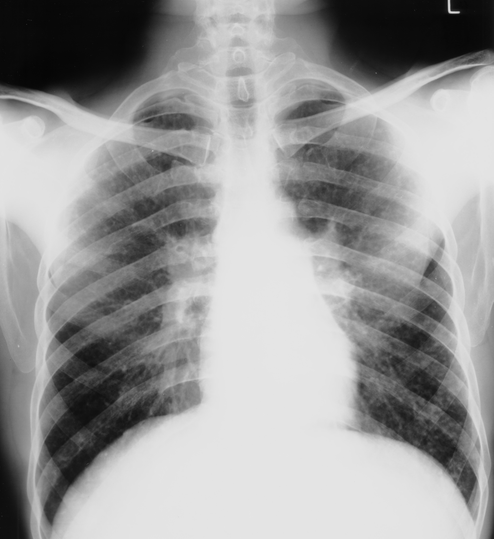

Bilateral hilar lymphadenopathy consistent with sarcoidosis